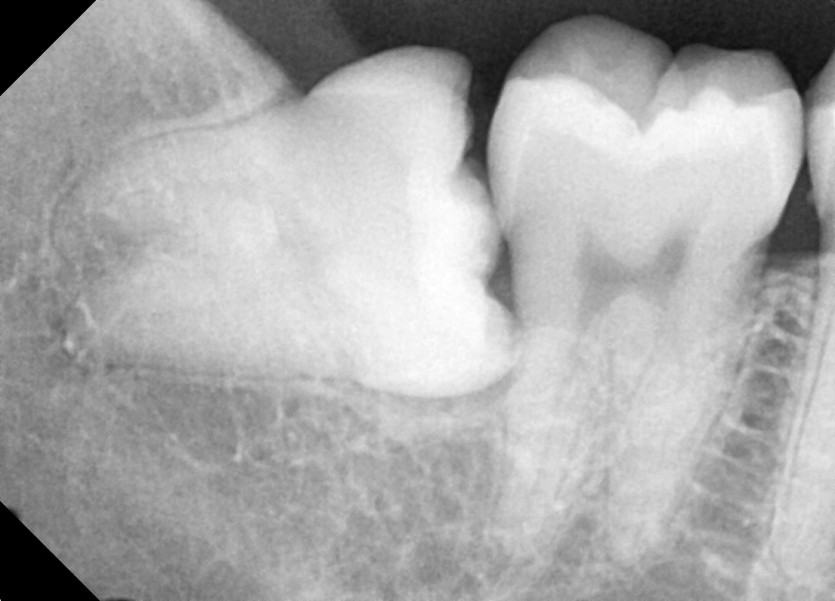

#18,28,38,48 사랑니 발치 (#19과잉치 포함)

구강 외과 전문의가 당일 발치했습니다.